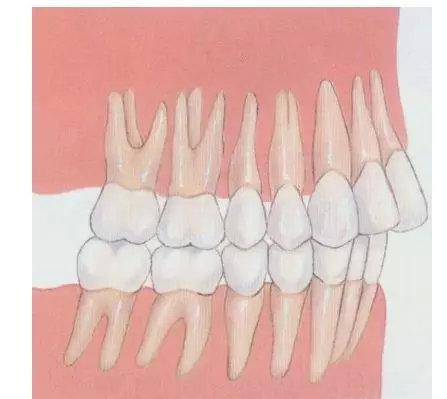

导致凸嘴的原因主要有两个,一个是牙性龅牙,主要是牙齿向外生长,或就是牙齿拥挤,导致门牙被挤出到队伍的前列,将嘴唇拱出来,自然就形成凸嘴了。

这样的问题,就要通过牙科正畸来矫正,也就是戴上牙套将牙齿重新排列整齐归位,矫正完成后会有很的改良。